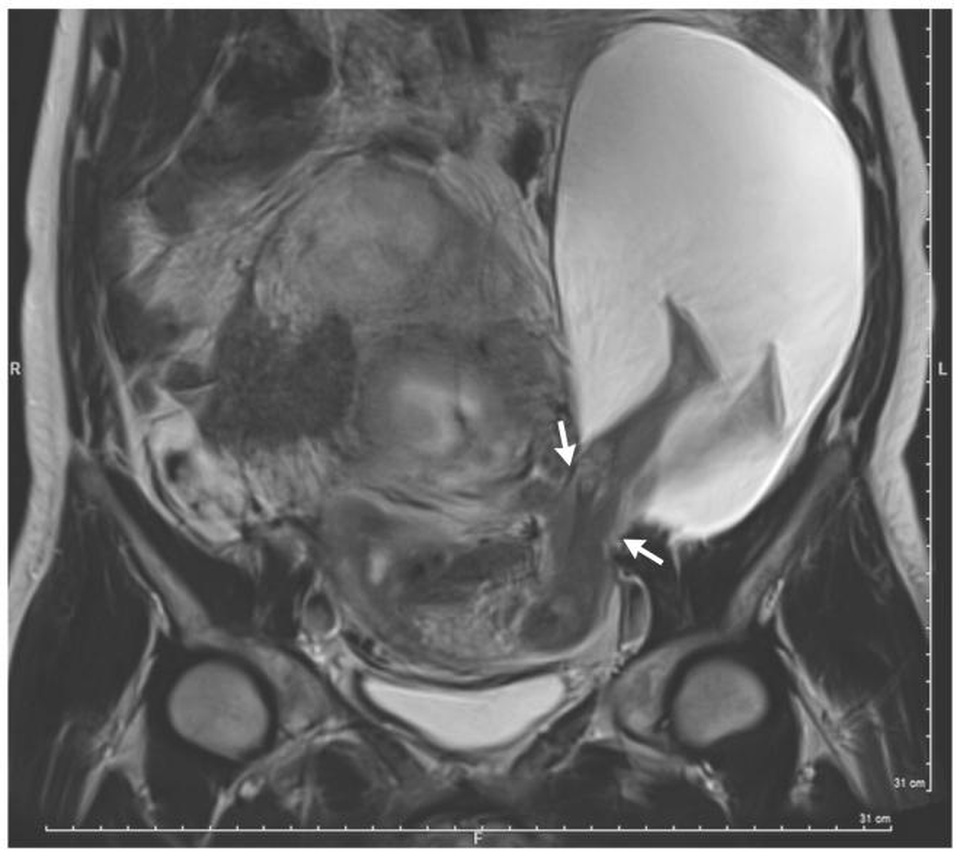

Như hình ảnh siêu âm ở tuần thứ 22 của một phụ nữ mang thai 33 tuổi cho thấy, một phần của túi ối có kích thước 19x12x9 cm đã thoát qua một lỗ ở thành tử cung. Hệ quả là chân của em bé đến trên đầu gối một chút đã thò ra ngoài thành tử cung và có thể tự do đạp trong bụng người mẹ.

Những hình ảnh siêu âm tiếp theo ở tuần 30 cho thấy vết rách đã đã tăng lên và thậm chí cơ thể của em bé lúc nào lọt ra ngoài tử cung nhiều hơn. Do mức độ nghiêm trọng của tình hình, và nguy cơ cho cả em bé và người mẹ, các bác sĩ đã quyết định mổ đẻ sớm ở tuần 30. Rất may một bé trai khỏe mạnh nặng 1,4kg đã chào đời.